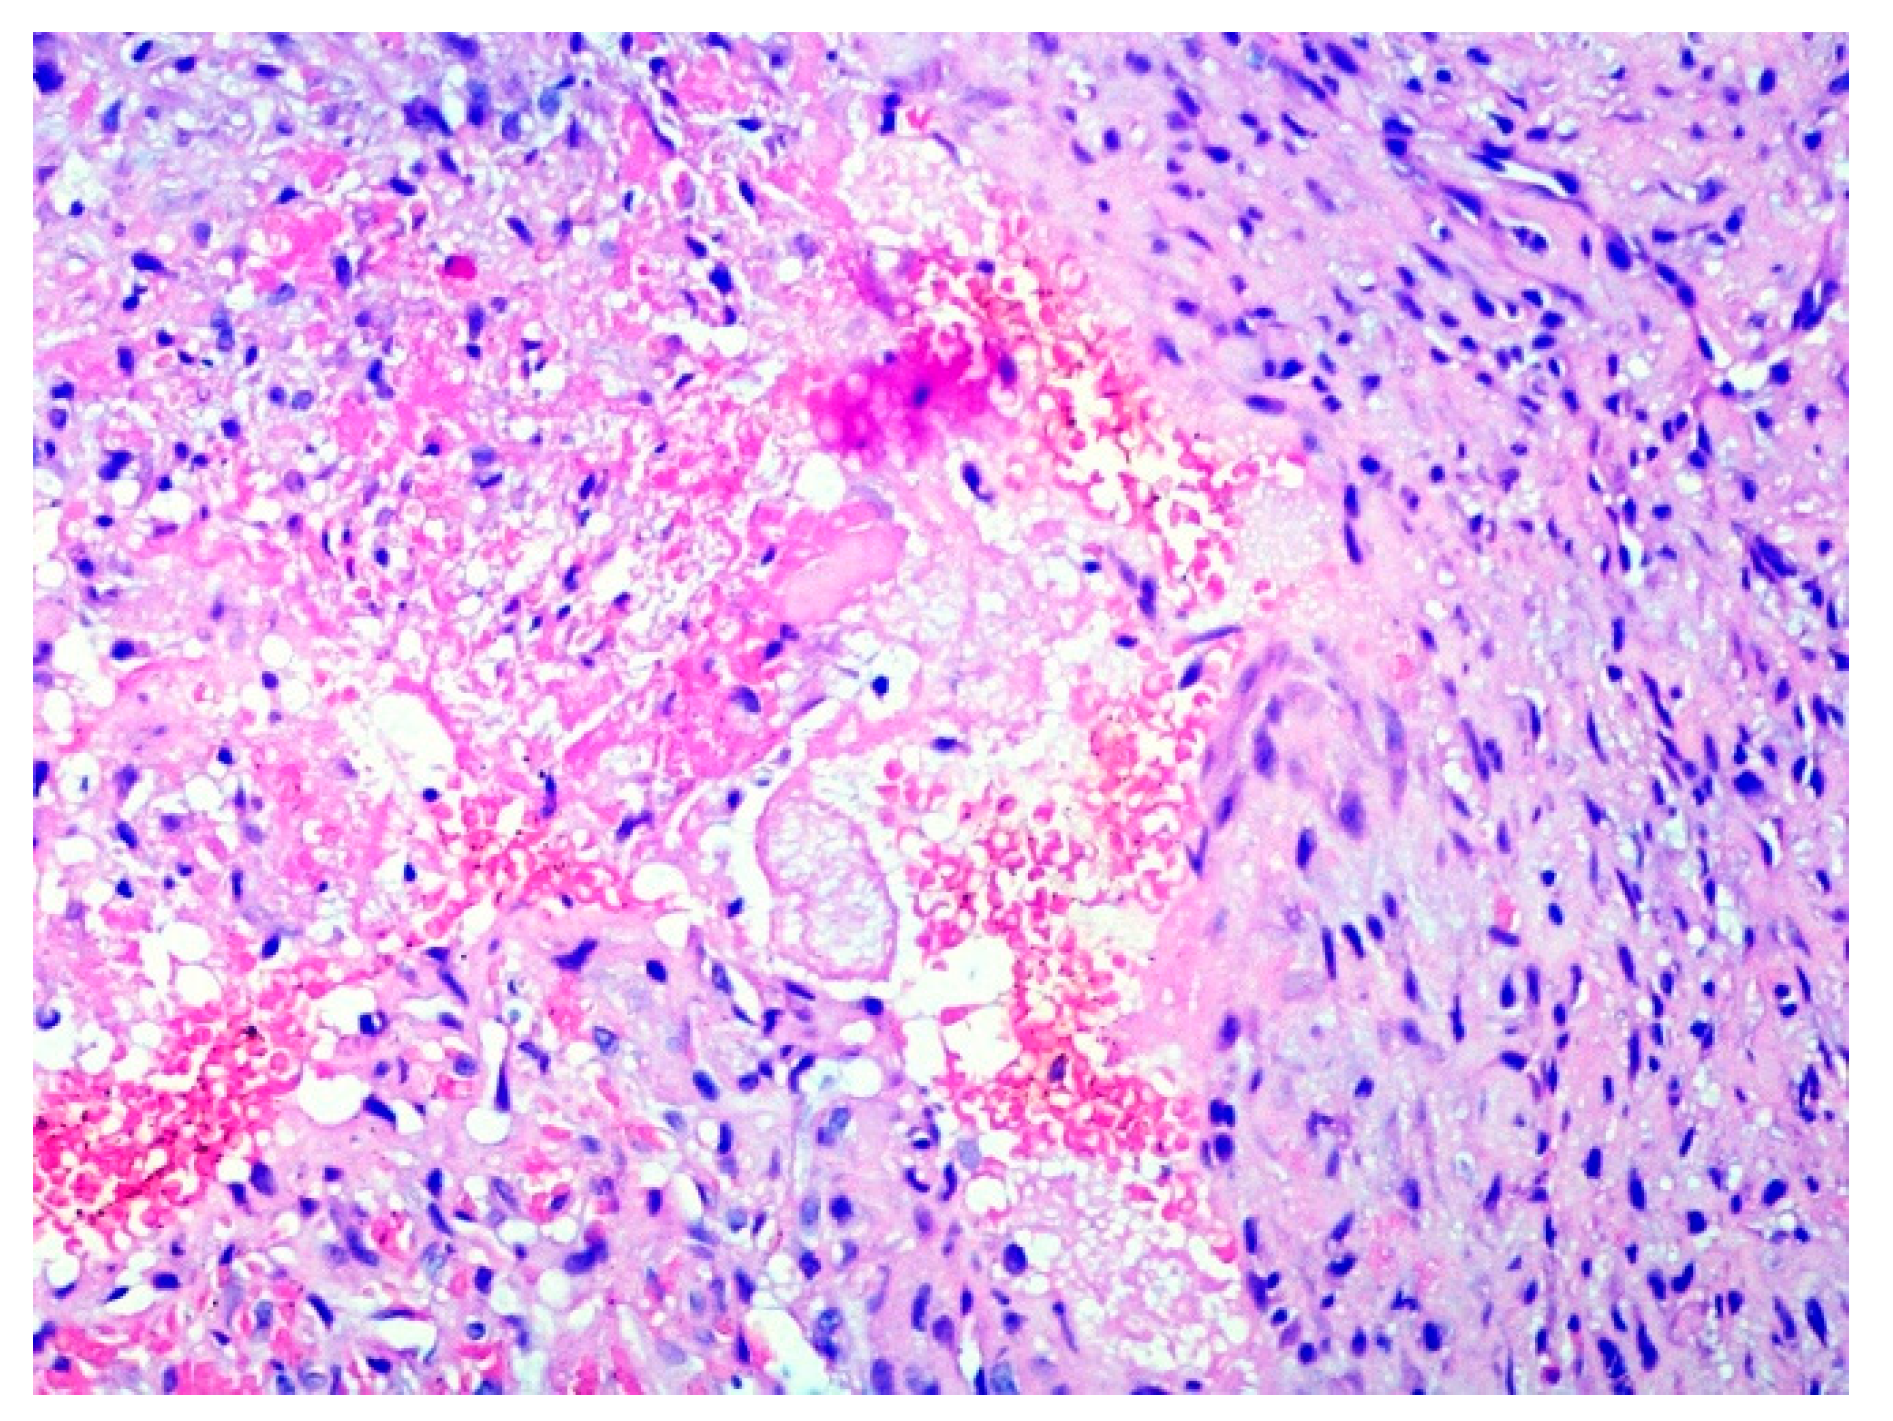

2. Case Presentation